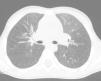

Después de la suspensión del tratamiento, los gemelos no presentaron ningún episodio destacable de infección pulmonar y disfrutaron de un crecimiento normal. La exploración física fue normal, al igual que la saturimetría. A la edad de 9 años se repitió la TCAR en el gemelo que tenía antecedentes clínicos más graves, y se observó una reducción de la neumopatía intersticial (fig. 4). Se realizó espirometría en ambos hermanos, que dio unos resultados apropiados para la edad.